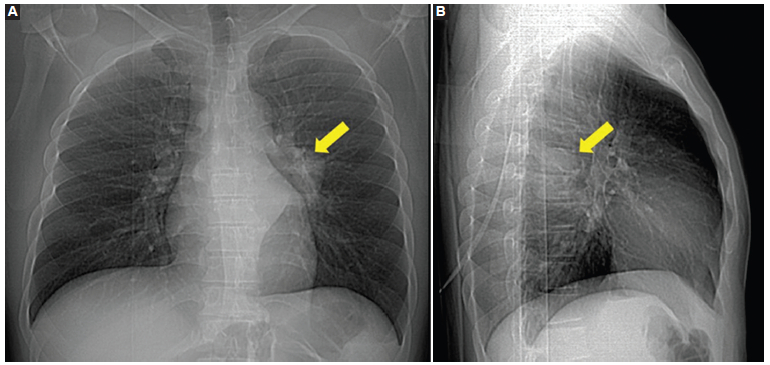

Se solicitaron radiografías de tórax de frente y de perfil, que mostraron una masa en el mediastino posterior (Fig. 1). Para mejor caracterización se realizó una tomografía computada (TC) de tórax, en la que se confirmó la presencia de una voluminosa tumoración sólida ubicada en el tercio medio del mediastino posterior, lateralizada a la izquierda, hipodensa, homogénea y con escaso realce del medio de contraste (Fig. 2). Desplazaba las estructuras mediastinales adyacentes, sin invadirlas, y por su sector posterior se introducía en el canal raquídeo. A pesar del amplio contacto óseo con los cuerpos vertebrales y los arcos costales, la única alteración observada fue en los arcos costales izquierdos, en los que producía un mínimo adelgazamiento de la cortical, sin interrupción de la misma.